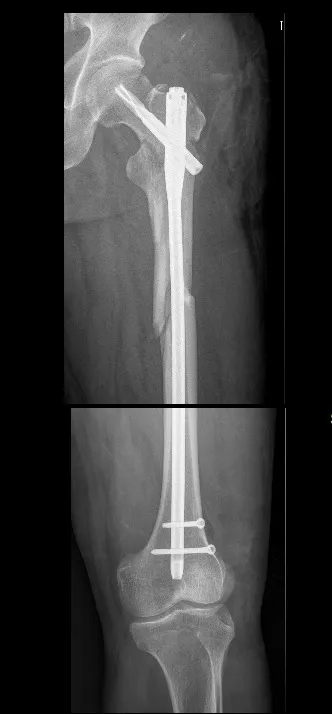

术后侧位看骨折块间仍有较大距离,但是我们不担心,骨折力线、颈干角没有太大问题。

术后两月半再看侧位,令人惊讶的事出现了,因为有软组织铰链夹板的保护,骨折块竟然向髓内钉周围汇聚到一起,骨折线完全消失。患者也完全能负重行走了。所以,遇到此类骨折,不管有多大难度,一定要最大程度的保护骨折周围软组织,让骨折块有活力,那样才能保证骨折顺利愈合。